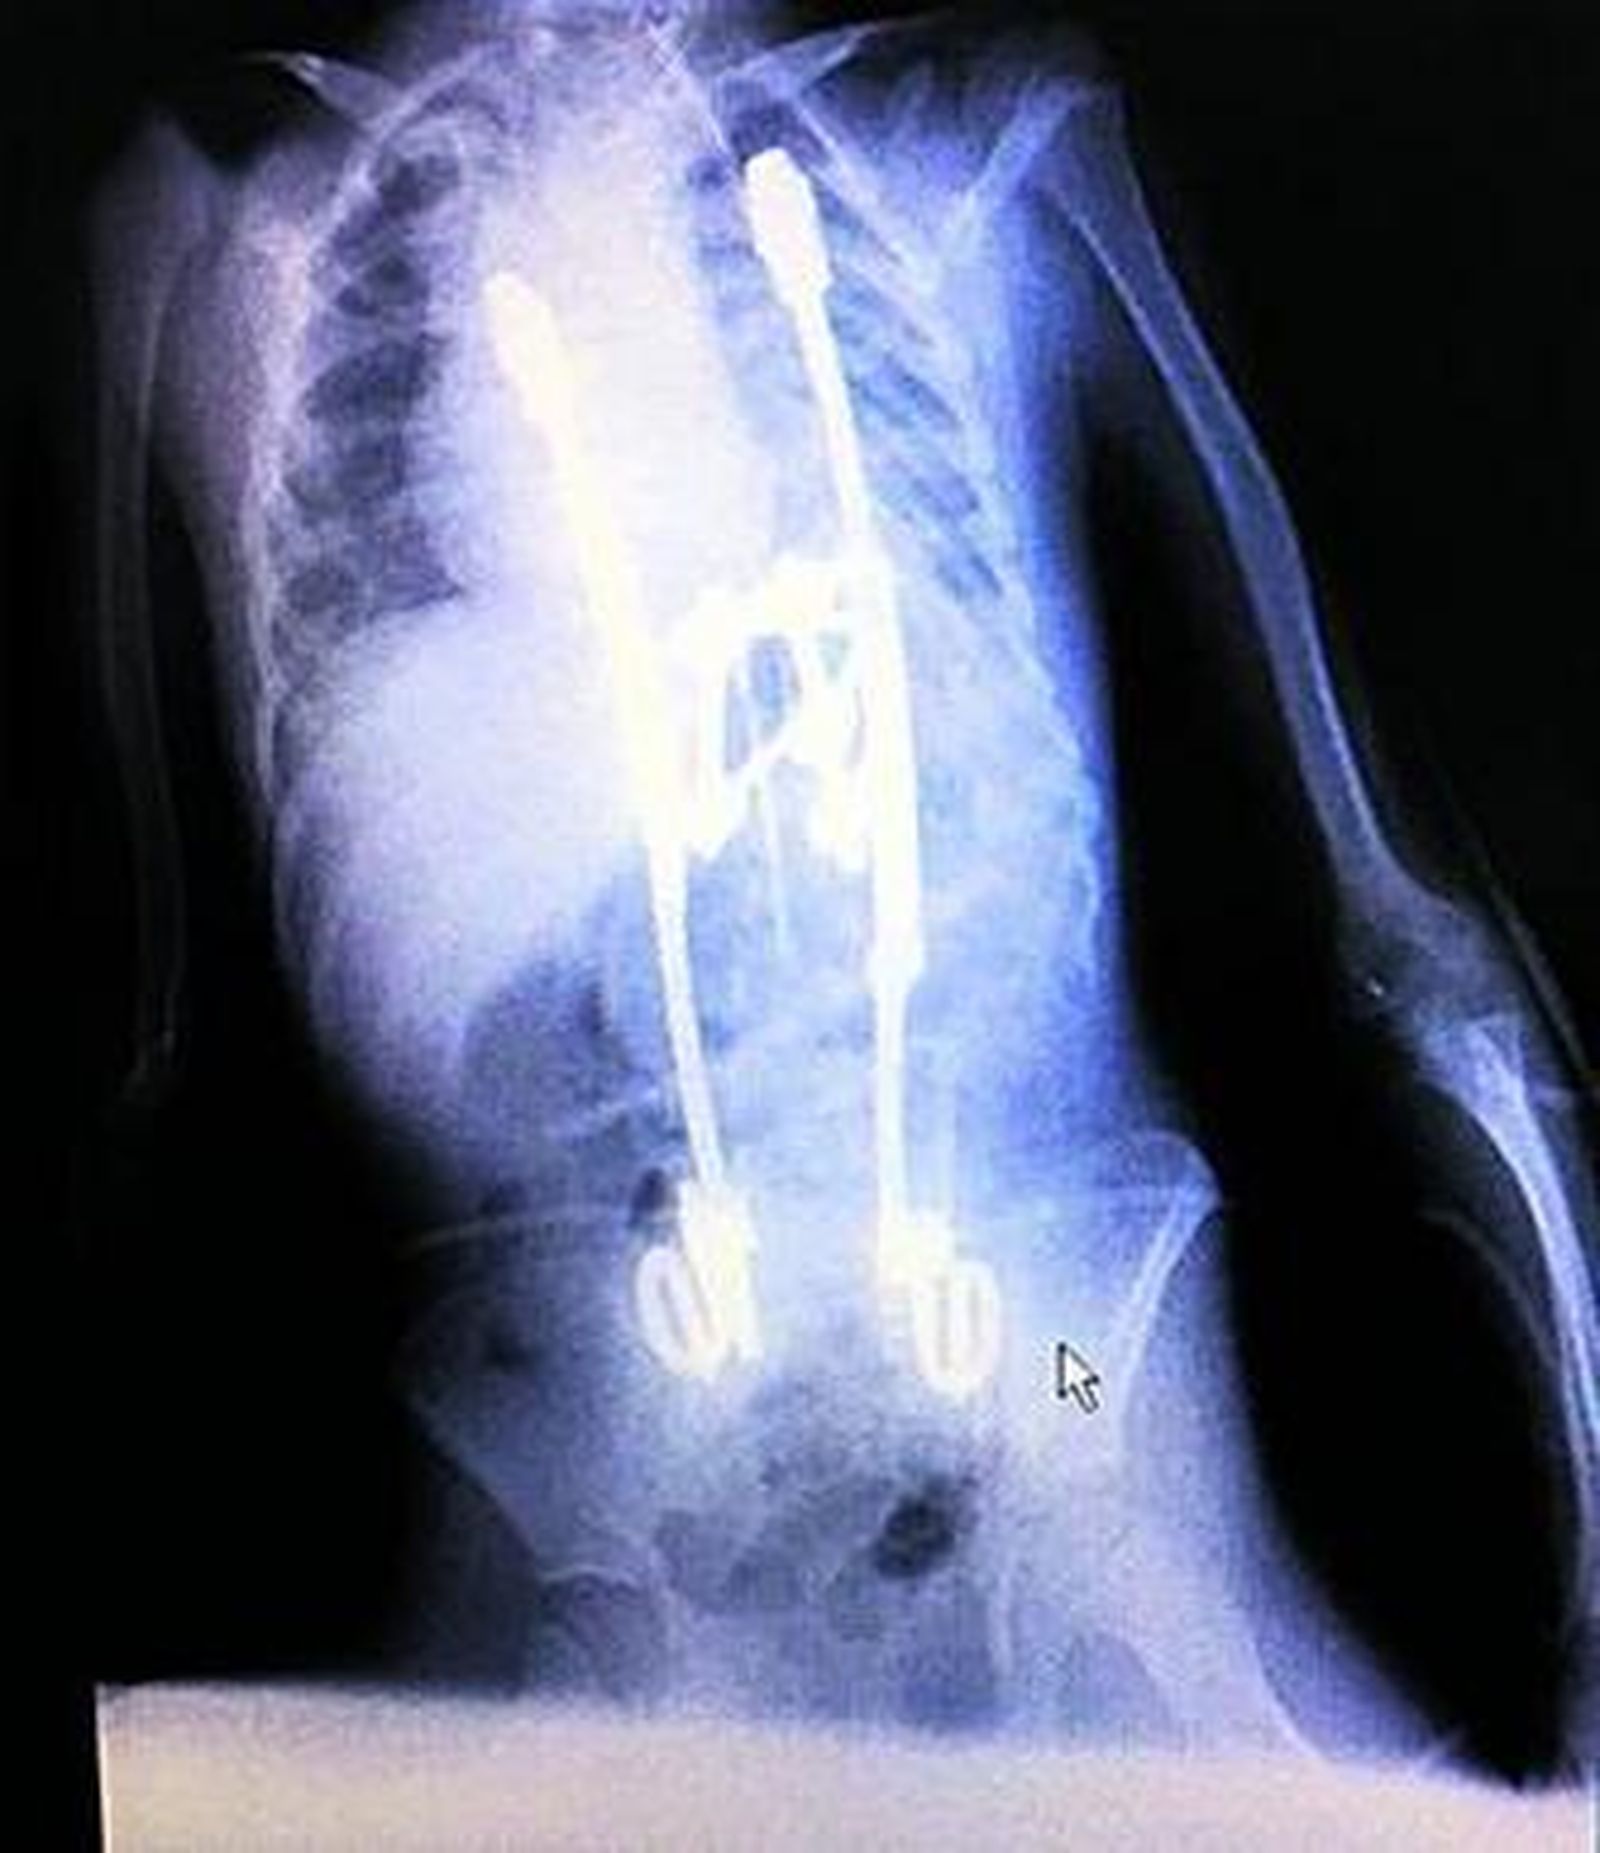

La incorporación de nuevas técnicas, así como la aparición de nuevos implantes, ha permitido ampliar las posibilidades quirúrgicas para problemas severos que afectan a la columna, que suelen causar incapacidad y dolor intenso. El aumento de la capacidad para intervenir casos de gran complejidad responde también, en gran medida, a la especialización, la coordinación y al alto índice de ocupación de los quirófanos (el 80% del tiempo en las cinco salas del raquis es ocupado por los actos quirúrgicos y apenas un 20% está dedicado a la preparación que incluye la limpieza así como el traslado del paciente). "Es fundamental eliminar los tiempos muertos de los quirófanos", explica el doctor Rovira, al incidir en que "estos tiempos muertos llegan a consumir casi la mitad de los días de quirófano".

Además de atender los casos del área hospitalaria Macarena, esta Unidad de Raquis también se encarga de casos complejos procedentes de otras provincias y comunidades autónomas. El mayor volumen de intervenciones en estos quirófanos se debe a problemas degenerativos de la columna vertebral (estenosis, hernias discales, enfermedad discal degenerativa y fracturas vertebrales); tumores y deformidades. "Hace unos 20 años los problemas por patologías degenerativas prácticamente dependían de tratamientos médicos (fármacos), pero ahora con los nuevos avances en los implantes se ha conseguido abordar estos casos mediante cirugías en procesos tan complejos como, por ejemplo, la sustitución de una vértebra", añade el especialista.

En cuanto a las deformidades más comunes destaca la escoliosis idiopática del adolescente que afecta principalmente a niñas de entre 12 y 15 años; seguidas por las hemivértebras (anomalía congénita en las vértebras). "Cada caso lo seleccionamos minuciosamente de modo que a la hora de entrar en quirófano estamos seguros al 100% de que vamos a mejorar la calidad de vida del paciente", añade el doctor Rovira. Los problemas severos de la columna suelen mermar en gran medida la vida de los afectados por el dolor y la discapacidad que genera para realizar tareas domésticas.